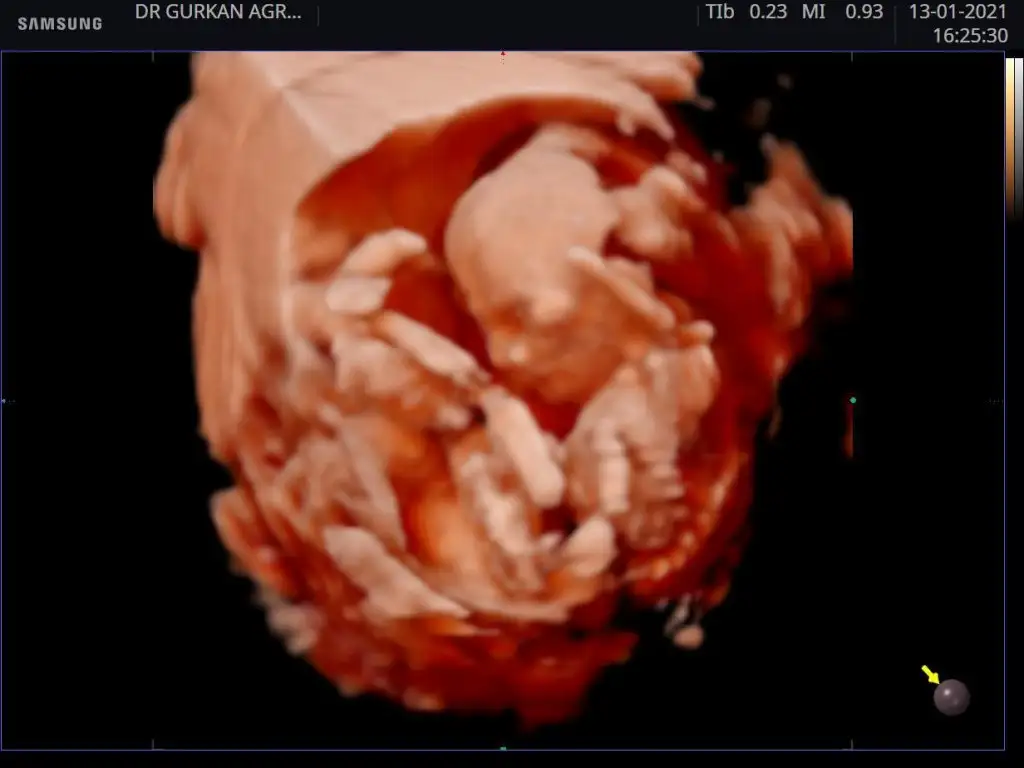

Bende bir kaç kişi diye baktırdım yorumları aynı bakalım sen ne diyeceksin kızkardeşimin 13 haftalık

13 haftalık doktor cinsiyeti söylemedi ama başkalarından tshmin aldim aynı cinsiyet i dediler bebek kardeşimin